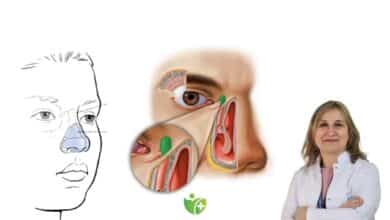

Gırtlak kanseri tanısında muayene

Bu muayenede burun veya ağız yoluyla kullanılan endoskopik görüntüleme yardımıyla gırtlak ve ses telleri ayrıntılı bir şekilde incelenir. Ses telleri üzerinde beyaz-gri renkli değişiklikler, düzensizlikler ve yaraların varsa belirlenir. Bu görüntüler muayene esnasında kayıt altına alınır; sonraki değerlendirme ve karşılaştırmalar için kullanılır. Sigara tiryakisi olan bir kişide yukarıda belirtilen lezyonlar aksi ispat edilene kadar kanser olarak kabul edilmelidir.